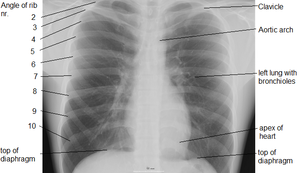

الحجاب الحاجز هو عبارة عن حاجز عضلى يفصل بين القفص الصدرى والتجويف البطنى (المعدة، الكبد، الأمعاء)

وهو عضلة مخططة ( اي من النو ع الذي تستطيع ان تتحكم به اراديا ) لكنه يمكن ان يتحرك بدون ان تتحكم به اراديا ايضا . فممكن ان تتحكم بسرعة التنفس فتبعث الاوامر من منطقة الحركة في قشرة المخ ، وعندما تنام فان الاروامر تستمر من ال Medulla و Pons وهي مراكز التنفس في الدماغ . تلتصق عضلة الحجاب الحاجز بالسطح الداخلي من الاضلاع الستة السفلى ، والفقرات الاثنين او الثلاثة الصدرية العليا ، واسفل عظم الصدر الامامي Xyphoid Process و Lumbosacral Ligament . تصعد الياف العضلة إلى فوق ثم تلتحم مع بعضهما في رباط في الوسط The Central Tendonوتكون في الجهة اليمنى اعلى من الجهة اليسرى ( المكان الذي تغطي فيه الكبد ) ويكون هذا الاختلاف واضحا في اشعة الصدر . عندما يأخذ المرء نفسًا يتقلص الحجاب الحاجز ويتحرك إلى أسفل، وهذا يزيد مساحة الفراغ في الصدر. وفي الوقت ذاته، فإن العضلات المرتبطة بالأضلاع تجعل الأضلاع تتحرك نحو الخارج. وهذا من شأنه أن يوسع الصدر ويخلق مع حركة الحجاب الحاجز باتجاه الأسفل فراغًا بسيطًا في الصدر. ويجعل هذا الفراغ الهواء يدخل الرئتين عبر القصبة الهوائية، وهذا العمل ىُدعى التنفس أو الشهيق. وفي أثناء الزفير يخرج الهواء من الرئتين، عندما ينبسط الحجاب الحاجز وعضلات الأضلاع. وعندما يتنفس المرء بشكل طبيعي، يكون الزفير في حالة سلبية والعضلات دون عمل. وتحتوي الرئة المتوسعة على ألياف مرنة كانت قد تمددت أثناء التنفس. وهذا النسيج المرن يشبه في سلوكه الخيوط المطاطية المشدودة، ويجعل الرئة تتقلص كالبالون المنكمش. وهذا يطرد الهواء خارج الصدر، وتصغر الرئة حتى تصل إلى الحجم الذي بدأ فيه التنفس. ولاتفرغ الرئتان بشكل كامل أثناء الزفير لأن جدار الصدر يبقيها في حالة متمددة جزئيًا. ويكون الزفير نشطًا أثناء التنفس الشديد الذي يحدث أثناء التمارين الرياضية. وهناك مجموعة أخرى من عضلات الأضلاع تساعد في جعل الصدر أصغر، كما أن العضلات في جدار البطن تتقلص لتدفع بالأعضاء البطنية إلى أعلى أمام الحجاب الحاجز، وتساعد بذلك على إخراج الهواء من الرئتين.

يغطي الحجاب الحاجز من الجهة العليا الملامسة للرئتين البطانة التي تبطن الصدر وهي ال Parietal Pleura ، و يكون الرباط المركزي ملاصقا لغلاف القلب The Fibrous Pericardium . اما من الجهة السفلى للحجاب الحاجز فانه يغطى بالغلاف المبطن للاحشاء في البطن و هو ال Perietal Peritoneum ما عدا في منطقة واحدة فانه يلامس سطح الكبد مباشرة وهذه المنطقة هي ال Bare Area و تقع في الفص الايمن من الكبد .